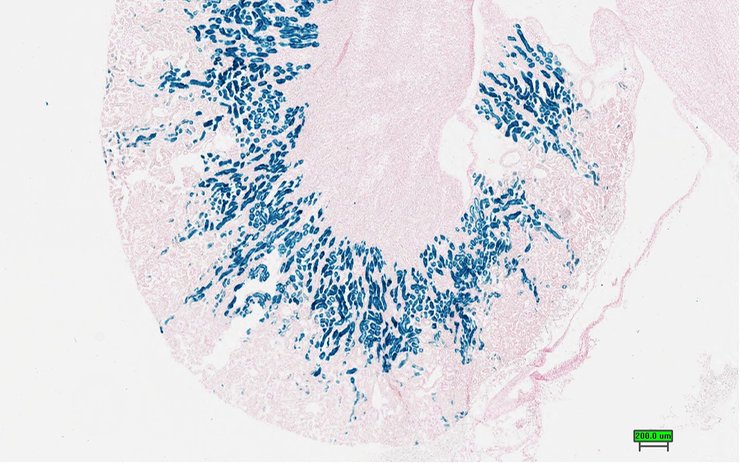

TS28: metanephros Present UC Davis_1866934 kidney

Specimen UC Davis_1866935: postnatal adult; Slc7a13tm1.1(KOMP)Vlcg/Slc7a13+ (more )

Structure Level Pattern Image Note

TS28: metanephros Present UC Davis_1866935 kidney

Specimen UC Davis_1866936: postnatal adult; Slc7a13tm1.1(KOMP)Vlcg/Slc7a13+ (more )

TS28: metanephros Present UC Davis_1866936 kidney

Specimen UC Davis_1866937: postnatal adult; Slc7a13tm1.1(KOMP)Vlcg/Slc7a13+ (more )

TS28: metanephros Present UC Davis_1866937 kidney

Specimen UC Davis_1866938: postnatal adult; Slc7a13tm1.1(KOMP)Vlcg/Slc7a13+ (more )

TS28: metanephros Present UC Davis_1866938 kidney

TS28: metanephros Present UC Davis_1866942 kidney

Specimen UC Davis_1866943: postnatal adult; Slc7a13tm1.1(KOMP)Vlcg/Slc7a13+ (more )

TS28: metanephros Present UC Davis_1866943 kidney

Specimen UC Davis_1866944: postnatal adult; Slc7a13tm1.1(KOMP)Vlcg/Slc7a13+ (more )

TS28: metanephros Present UC Davis_1866944 kidney

Specimen UC Davis_1866945: postnatal adult; Slc7a13tm1.1(KOMP)Vlcg/Slc7a13+ (more )

TS28: metanephros Present UC Davis_1866945 kidney